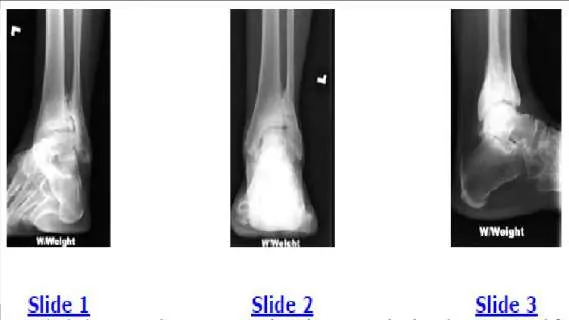

Question 47:

A 44-year-old obese man presents for treatment of acute ankle pain. He does not have a history of trauma or a systemic history of note. His opposite foot has had multiple episodes of acute pain in the past, lasting from 3 to 5 days. On examination, the ankle is warm, swollen, and exquisitely tender to palpation and any range of motion (Slide1, Slide 2, and Slide 3). Concerned about the source of pain, you aspirate the joint and send the sample for analysis. You expect to find:

Options:

- Gram-positive cocci

- Gram-negative rods

- Normal joint fluid

- Sodium monourate crystals

- A high red cell count

Correct Answer: Sodium monourate crystals

Explanation:

This patient most likely has an acute attack of gout. The prior episodes of foot pain and the sudden onset lasting 5 days for each bout is characteristic. The ankle is not a common location for gout (the most frequent site is the hallux metatarsophalangeal joint). The treatment should consist of injection of a corticosteroid into the joint and administration of appropriate oral anti-inflammatory medication.